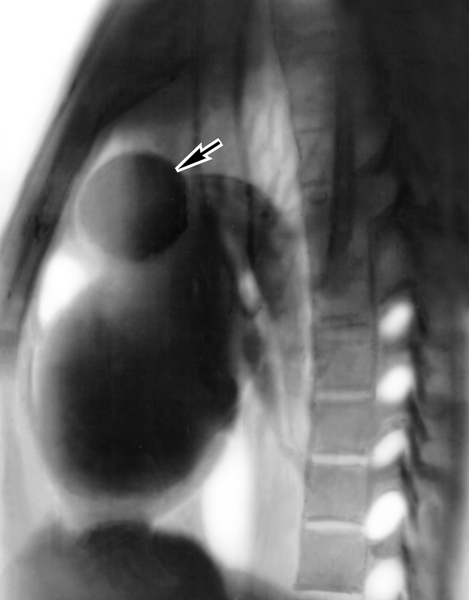

Рентгеновские снимки тератомы средостения: Диагностика и лечение

Раздел: Фотоэссе